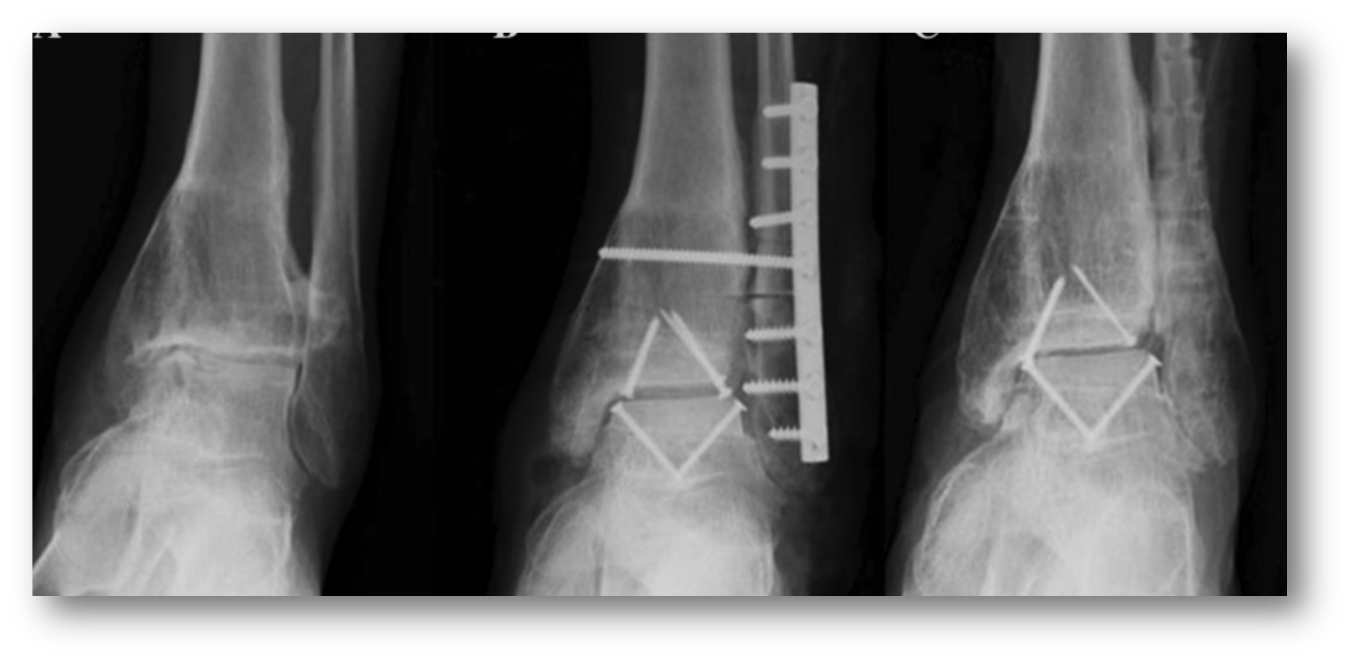

In very severe cases we can replace part of a damaged ankle with a fresh cadaver graft. The was this works is we take a CT scan and xrays of a patients ankle, then a special lab finds a donor match of an ankle with the same dimensions. we then cut a peice of the cadaver bone and cartilage and use it to replace a damaged ankle joint . The xrays below shoe on the left a severely arthritic ankle joint .the next two xrays show screws holding in a cadaver ankle. We replaced the entire ankle with a cadaver ankle joint. again patient selection is of utmost importance for this advanced procedure.